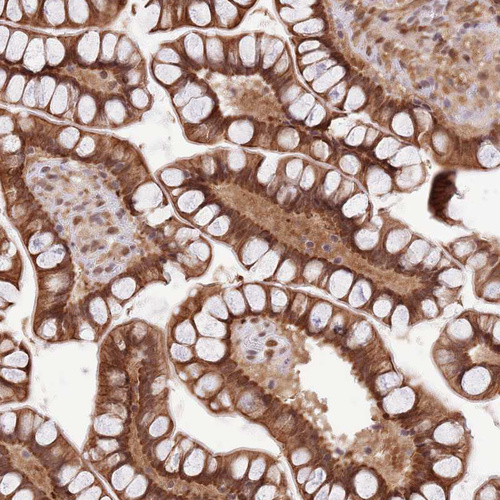

Immunohistochemical staining of human skeletal muscle shows strong cytoplasmic positivity in myocytes.